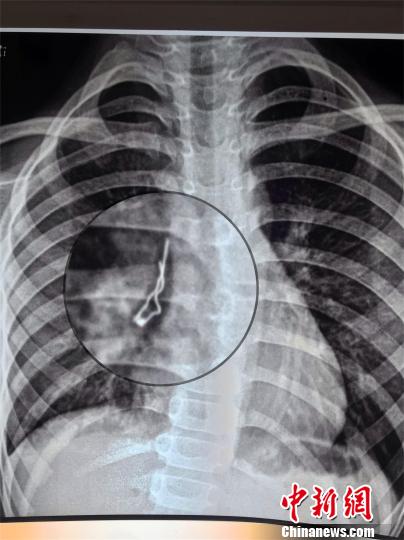

中新網(wǎng)武漢6月13日電 (周建躍 溫紅蕾 黃潔瑩)湖北咸寧7歲男孩小路(化名)咳嗽一周不見(jiàn)好,到醫(yī)院檢查發(fā)現(xiàn)有個(gè)不明金屬物體卡在肺部右中間支氣管。湖北省婦幼保健院兒內(nèi)科醫(yī)生12日通過(guò)手術(shù)取出一個(gè)LED發(fā)光二極管,幸好該二極管是尖頭朝上沒(méi)有扎穿肺。

原來(lái),小路吞下去的是個(gè)LED發(fā)光二極管,長(zhǎng)約2.6厘米,寬7毫米。醫(yī)生介紹,這個(gè)二極管在小路肺里呆了一周,幸好鐵絲頭朝上,沒(méi)有扎穿肺。如果鐵絲朝下,隨著呼吸運(yùn)動(dòng),尖頭隨時(shí)有可能刺傷氣管,引起肺部出血或者氣胸等嚴(yán)重的致死性并發(fā)癥。

男孩誤吞LED發(fā)光二極管 深入支氣管險(xiǎn)些扎破肺LED發(fā)光二極管卡在小路肺部右中間支氣管。院方供圖